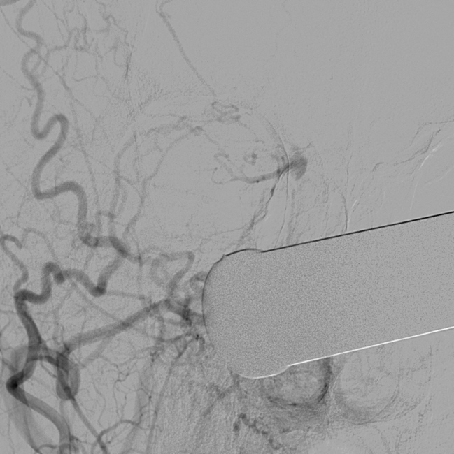

2014-9-29 DSA

介入手术:(缺Fagarty /Merci/ Penumbra球囊导管、带膜支架)颈内动脉颅内外段置球囊保护,拔异物。

问题:1、颈内动脉破裂处理?2、取栓再通,如何防止血栓脱落?

颈内动脉破裂:远近断结扎

颈内动脉未破裂:探查,排栓;再通需立即血管造影排除假性动脉瘤或夹层,并定期复查;未能再通需Penumbra管取栓(风险大!)。